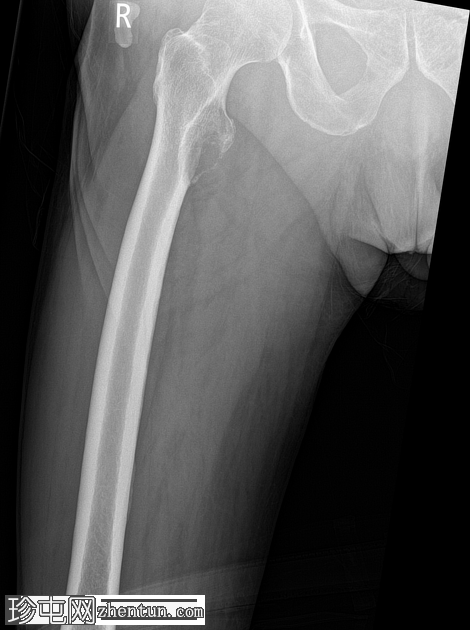

右股骨近端小转子水平处出现溶骨性病变,病变呈扩张性,并伴有皮质破坏。鉴于已知甲状腺恶性肿瘤伴骨转移病史,推测为转移性病变。无病理性骨折。

建议骨科/肿瘤科诊治。